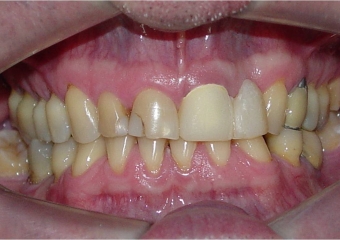

Prótese fixa em porcelana sobre implante Cone Morse

Imagem final, do caso terminado em fevereiro de 2013